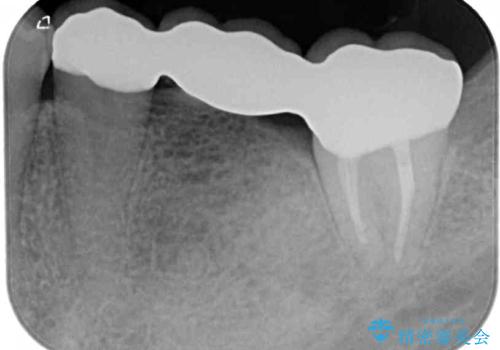

まずは奥歯の痛みを改善し、その後矯正治療を行い、最後にオールセラミックブリッジによる補綴治療を行うこととしました。

むし歯をきっかけに矯正治療を行うこととなりましたが、学生の頃から気になっていた歯列を改善することができ、患者様には大変満足していただけました。